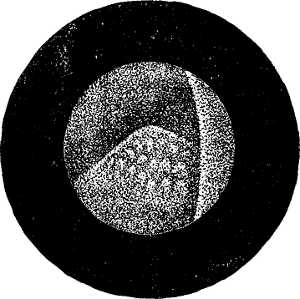

| XII. SURGERY.—Papillomatous Tumor of the Bladder, demonstrated by Means of Lister's Electro-cystoscope.—By F. N. Otis, M.D.—An interesting instance of the use of an exploratory electric light.—2 illustrations. | 10354 |

| Tumors of the Bladder Diagnosed by Means of the Electro-Endoscopic Cystoscope.—By Dr. Max Nitze.—The same general subject in further detail, giving the German practice.—5 illustrations. | 10353 |